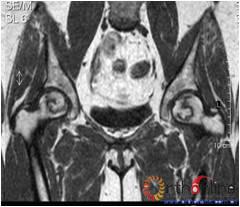

病灶修复情况比较,加用BMP2组病灶修复的完全性及硬化骨数量普遍优于未加BMP2组。(图3)

图3-2 女,30岁,SARS患者骨坏死,(1)术前MRI示双侧骨坏死;右Ⅱc期C3型,左Ⅱb期B型,打压植骨术(加BMP2),(2)5年后CT显示病灶修复好,关节功能优